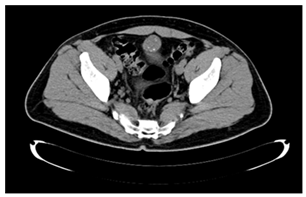

The evaluated tissue was processed with the technique conventional histological (sections were made 3 microns to stain with hematoxylin and eosin). A neoplasm with groups was identified of glandular lights, mucosecretor epithelium with nuclei polarized at the base, clear cytoplasm, coexistence of mucin and areas with epithelium of Transitional type, which infiltrated adipose tissue adjacent, associated with desmoplastic reaction (inflammation and peritumoral fibrosis) (Figure 4). The sample was sent to an antibody label of cytokeratin 7, which was positive-membranous (+++), cytokeratin 20 (+++), CDX2 positive-nuclear (+++) and prostate antigen specific negative. This immunophenotype is expressed in glandular tumors of urachal origin, with glandular growth pattern, so the positivity of cytokeratin 7 rules out the gastrointestinal metastasis and the negativity for the prostate antigen rules out the possibility of metastasis of prostatic origin. Open surgical treatment was performed, accessing by the middle line, where it was found peritoneal carcinomatosis. Cystectomy was performed partial and en bloc resection of the urachus, besides lymphadenectomy and omentectomy.

Figure 4 Cytology showing groups of glandular lights, mucosecretor epithelium with nuclei polarized at the base and clear citoplasm.

The histopathology report was: adenocarcinoma mucoproducer with scarce tubular glands, moderately differentiated, which affected the mucosa and the wall to the muscular layer of the bladder, in addition to two tumor implants in the omentum of 3 and 5 cm. The lymph nodes showed, only, sinusoidal hyperplasia reactive. The patient received adjuvant chemotherapy with cisplatin and gemcitabine. After 10 months of treatment the disease persisted, with ganglionar activity on the left side of the vneck, ipsilateral armpit, just like in the area para-aortic and hepatic, so the scheme to paclitaxel and carboplatin. Adverse effects caused by chemotherapy they were little tolerated by the patient; by so, he decided to suspend the treatment after one month after starting it. At present receives chemotherapy with capecitabine for palliatives and tramadol-paracetamol to control the pain.